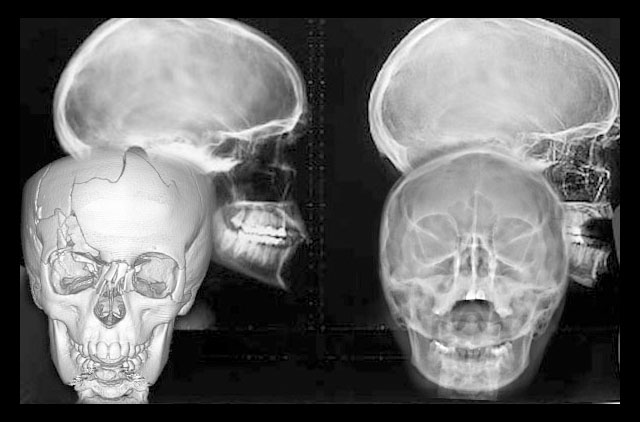

Tomografía 3D (Disponible en sucursal Guelatao y Roma)

La diferencia radical entre la tomografia cone-beam (TCB) y la tomografia computarizada (TC) es la forma de procesar la imagen, es decir la TC es generada a partir de imagenes 2D en la cual se producen aberraciones o distorsiones, sin poder usarla con un poder fidedigno, en cambio la TCB la reconstruccion se hace a través de cortes, sin provocar distorsiones, deja una escala 1:1.

Estudio completo de ortodoncia en 3D (cone-beam) digital CD

-Panoramica (OP)

-Lateral de Craneo (LC)

-Modelos de Estudio en yeso con caja plática rígida

-Trazos Cefalométricos, tomografía volumétrica cone-beam

-Fotografía Digital e Impresa

-10 Tomas Digital Modelos en CD